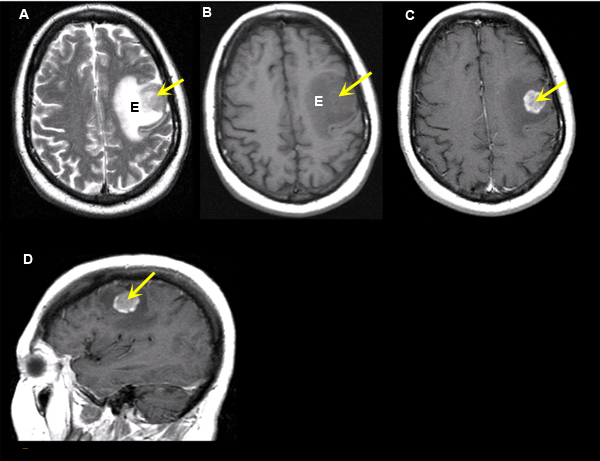

Medullary tumors are the third most common of all thyroid cancers and together make up about 3% of all thyroid cancer cases. Cancers that have spread (metastasized) to the brain from other locations in the body are known as brain metastases. Learn about thyroid cancer diagnosis and treatment, including thyroid surgery, radioactive iodine and thyroid radiation therapy treatments to the head and neck increase the risk of thyroid cancer. Differentiation refers to how abnormal the cells look under a microscope rare cases have been described that have spread to the adrenal glands and brain.